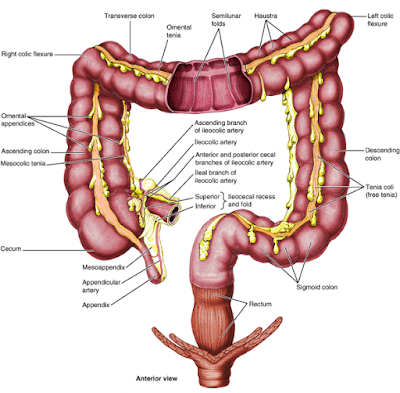

Απόφραξη δωδεκαδακτύλου:

– Καρκίνος δωδεκαδακτύλου

– Καρκίνος κεφαλής του παγκρέατος

– Ατρησία σε νεογνά

Απόφραξη λεπτού εντέρου:

– Συμφύσεις

– Περίσφιξη κήλης

– Όγκοι λεπτού εντέρου

– Εκκόλπωμα Meckel

– Εγκολεασμός του εντέρου

– Συστροφή εντέρου

– Νόσος Crohn

Απόφραξη παχέος εντέρου:

– Περίσφιξη κήλης

– Όγκοι

– Εκκολπωματίτιδα

– Συστροφή

– Κοπρόσταση